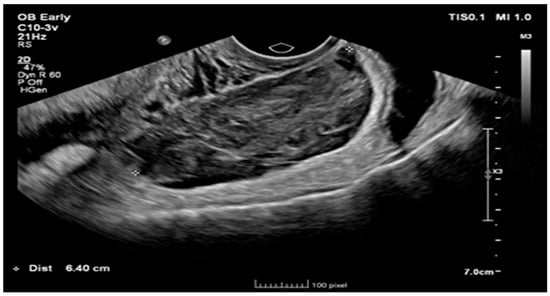

Ruptured Heterotopic Pregnancy: Laparoscopic Management, Preserving Intrauterine Viability

Pregnancy (HP), defined as the coexistence of intrauterine and ectopic gestations, is a rare condition, especially in spontaneous conception, but it is a life-threatening obstetric emergency when rupture occurs, with a reported maternal mortality rate of 0.03%. Diagnosis is often delayed because confirmation of an intrauterine pregnancy can mask clinical signs of a concurrent ectopic gestation. Early recognition and prompt surgical intervention are therefore critical to maternal safety and preservation of intrauterine viability. This case highlights the diagnostic challenges and successful management of a spontaneous ruptured heterotopic pregnancy. Case presentation: A 34-year-old Middle Eastern woman, gravida 4, with a spontaneous conception, presented with sudden severe lower abdominal pain and signs of acute hemoperitoneum (hypotension, tachycardia, and marked peritoneal signs). Transvaginal ultrasound demonstrated a viable intrauterine pregnancy at 9 weeks 4 days gestation, together with a ruptured left tubal ectopic pregnancy of similar gestational age. The patient underwent urgent laparoscopic left salpingectomy with evacuation of approximately 1200 mL of intraperitoneal blood and clots. Postoperatively, she developed significant anemia (hemoglobin drop from 11.2 g/dL on admission to 6.5 g/dL) requiring transfusion of four units of packed red blood cells. Serial ultrasonographic follow-up confirmed ongoing viability of the intrauterine pregnancy, which ultimately resulted in a live birth at term. Progressive resolution of the postoperative pelvic hematoma was also noted. Conclusions: Ruptured heterotopic pregnancy remains a diagnostic and therapeutic challenge. This case, along with a synthesis of the contemporary literature, demonstrates that a high clinical index of suspicion, timely ultrasound diagnosis, and immediate minimally invasive surgical management are paramount. Furthermore, rigorous postoperative monitoring and resuscitation, including targeted transfusion, are essential to achieve maternal stabilization while allowing continuation of a viable intrauterine pregnancy, with reported live birth rates exceeding 70% following timely intervention. Full article